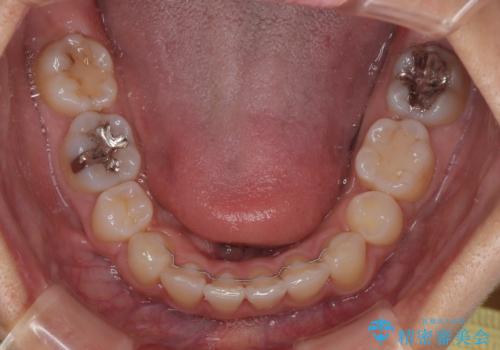

- 前歯のクロスバイトと口元の膨らんだ横顔の印象を気にして来院された患者様です。

しかしながら。そのまま叢生を解消すると横顔が突出した印象になる可能性が高かったため、上下左右の小臼歯4本を抜歯して、ワイヤー装置にて矯正治療を行うこととしました。

上下左右の第一小臼歯4本を抜歯して治療を行うことがセオリーでしたが、左下は第二小臼歯が銀歯であったため、イレギュラーではありますが、そちらを抜歯しました。

その影響で治療期間は長くなりましたが、処置していない歯を保存することができました。